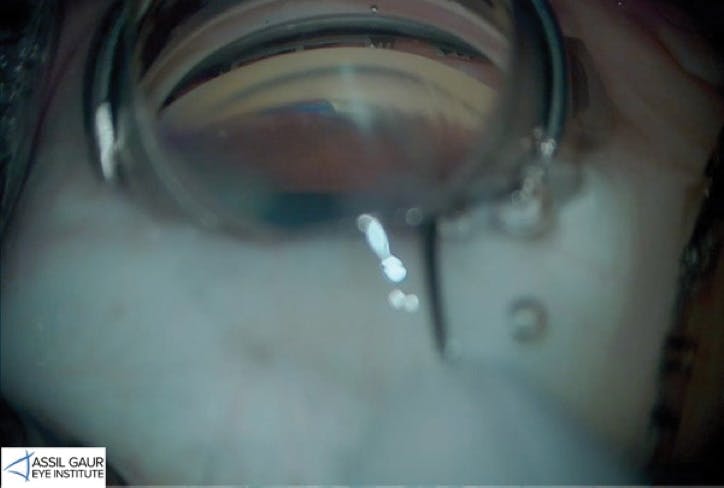

In my view, OMNI is a consideration across the spectrum of primary open-angle glaucoma as long as there is a good view of the trabecular meshwork and no compromise of the angle structure such as neovascularization. In combination cases, when OMNI is performed at the time with cataract surgery, the patient benefits from two mechanisms for intraocular pressure lowering (IOP): drainage pathways tend to open after a cataract is removed, and then I use the OMNI to reinstate more flow and salvage the aqueous drainage pathways and collector channels (Figure 1).

Figure 1. A patient with moderate primary open-angle glaucoma who was on 3 medications presented with a visually significant cataract. She underwent cataract surgery and a 360º viscocanaloplasty with 180º goniotomy using the OMNI surgical device. She was able to achieve 20/20 vision with the implantation of a toric IOL, and she eliminated all three of her glaucoma medications. (Image courtesy of Avneet K. Sodhi Gaur, MD)